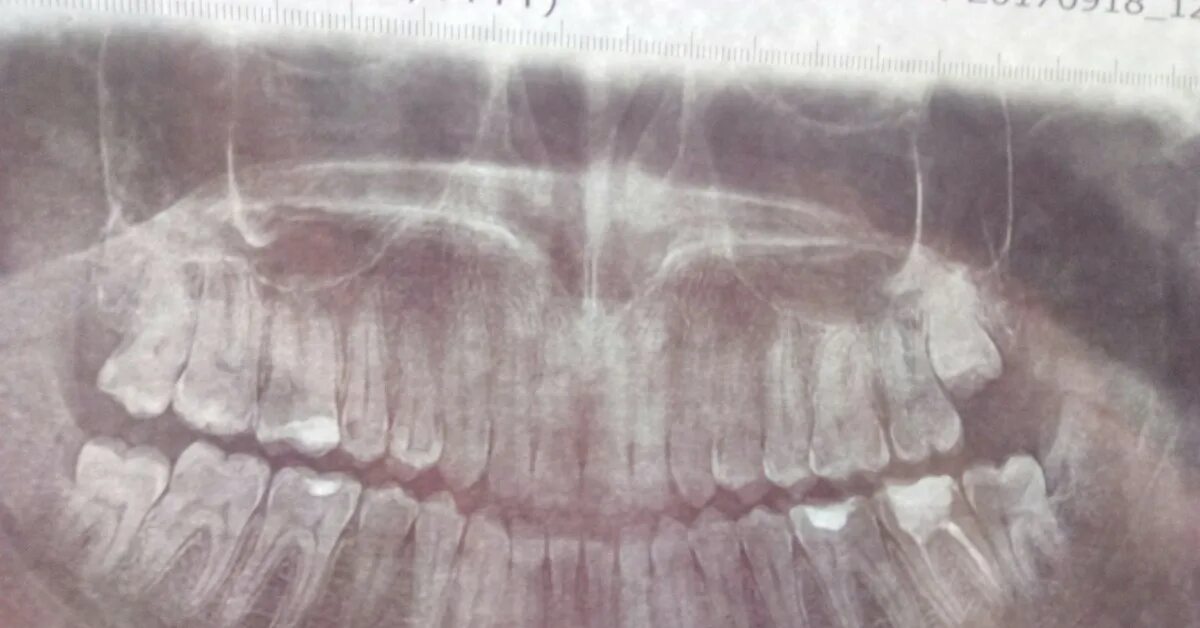

Eight teeth